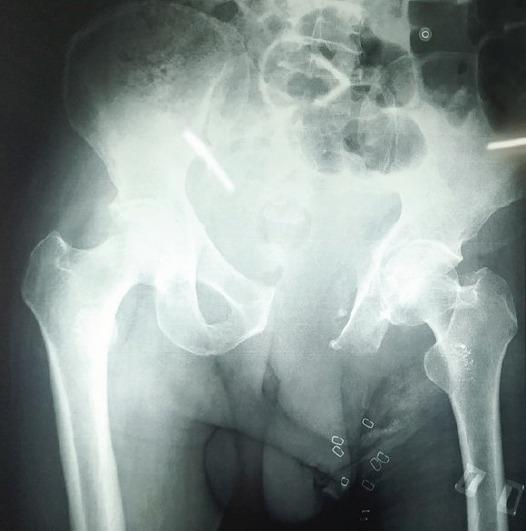

A 60-year-old male presented with a colossal swelling at groin reaching up to distal thigh. He was walking with a wide-based gait due to pain and discomfort. 30 year back, the patient first reported this swelling of pea size, for which he was advised surgery but due to fear of surgery and economic reason he refused. Swelling gradually increased in size and reached up to distal thigh in the past 30 years. It was hard and non-tender up to 6 months back, when suddenly a change in consistency from hard to soft in distal area was noticed. On examination, a large soft cystic swelling was hanging from his pubic area. Tumor was fixed at base on proximal end. On magnetic resonance imaging, size of tumor was 281 mm in length, 263 mm in width, and 250 mm in anteroposterior diameter. Tumor was arising from superior and ischiopubic rami. However, no intra-articular extension was seen. A radiographic skeletal survey and bone scan did not reveal any other lesion. On biopsy, chondrogenic tumor composed of lobules of chondroid material with no cellular atypia or evidence of malignancy was reported. Considering the age of patient, rapid progression in recent months, size and duration of tumor, and type 3 pelvic resection was planned. Using utilitarian pelvic incision with perineal extension, separating long adductor muscles and deep femoral artery tumor, tumor excised with osteotomy at pubic symphysis, and on superior and inferior pubic rami. With minor wound complications, wound healed in 3 weeks. Post-operative biopsy reported as Grade 1 chondrosarcoma. At 3-year follow-up, the patient has no complains and no sign of recurrence noticed.

一名60岁男性,腹股沟处出现巨大肿胀,一直延伸至大腿远端。由于疼痛和不适,他走路时呈宽基步态。30年前,患者首次报告豌豆大小的肿胀,当时建议他手术,但由于害怕手术和经济原因,他拒绝了。在过去30年里,肿胀逐渐增大,直至大腿远端。直到6个月前,肿物一直坚硬且无压痛,之后远端区域突然出现质地从硬变软的变化。检查时,一个巨大的软囊性肿物从耻骨区垂挂下来。肿瘤在近端基部固定。磁共振成像显示,肿瘤长径281毫米,宽径263毫米,前后径250毫米。肿瘤起源于耻骨上支和坐骨耻骨支。然而,未见关节内侵犯。影像学骨骼检查和骨扫描未发现其他病变。活检报告为软骨性肿瘤,由软骨样物质小叶组成,无细胞异型性或恶性证据。考虑到患者年龄、近几个月的快速进展、肿瘤大小和病程,计划行3型骨盆切除术。采用带会阴延长的实用型骨盆切口,分离长收肌和股深动脉,在耻骨联合处以及耻骨上、下支行截骨术切除肿瘤。术后伤口出现轻微并发症,3周后愈合。术后活检报告为1级软骨肉瘤。在3年随访中,患者无不适主诉,未发现复发迹象。